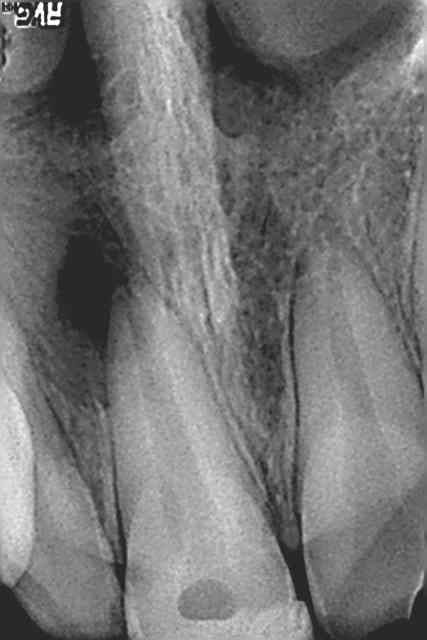

L'obturation est pas mal. Un bonchon de MTA aurait peut être été plus sur mais 70 cela ne m'impressione pas outre mesure, on a des rte ou l'apex a été élmiminé ou l'on arrive a ces diamètres.

tres joli boulot.

Mais l'obturation est très belle !

Beau travail

A part surveiller par des contrôles radios, il n'y a pas grand chose à faire de plus pour le moment.

L'avenir te dira quoi faire (en particulier si début de résorption), RTE rétrograde si nécessaire plus tard mais laisse faire la nature pour le moment.

Un bouchon de MTA poussé directement en intracanalaire aurait peut être été mieux mais ce n'est pas si simple que cela à mettre en place, d'autant plus que cela ne se condense pas vraiment (enfin ce n'est pas la même sensation qu'un IRM). Cela dépend aussi de la longueur de ton incisive. Si elle était longue, tu aurais été limité par la longueur de ton MTA gun. Comme ton canal était apparemment bien large, cela aurait pu être jouable.

Sinon, on est tous d'accord pour dire que tu as bien bossé.